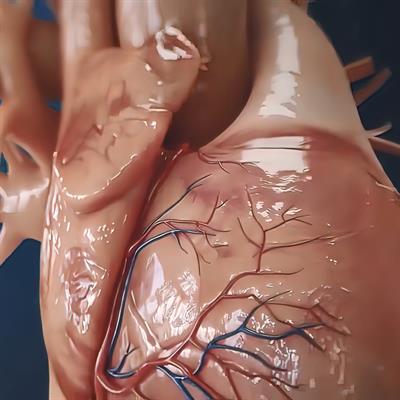

Inflammatory Cardiomyopathy: From Pathogenesis To Precision Therapy